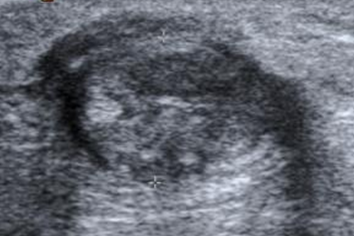

Fig 82. Tendinosis crónica del aquiles.

Ecografía vista axial. Engrosamiento del tendón con alteración de su ecogenicidad, por inflamación crónica.